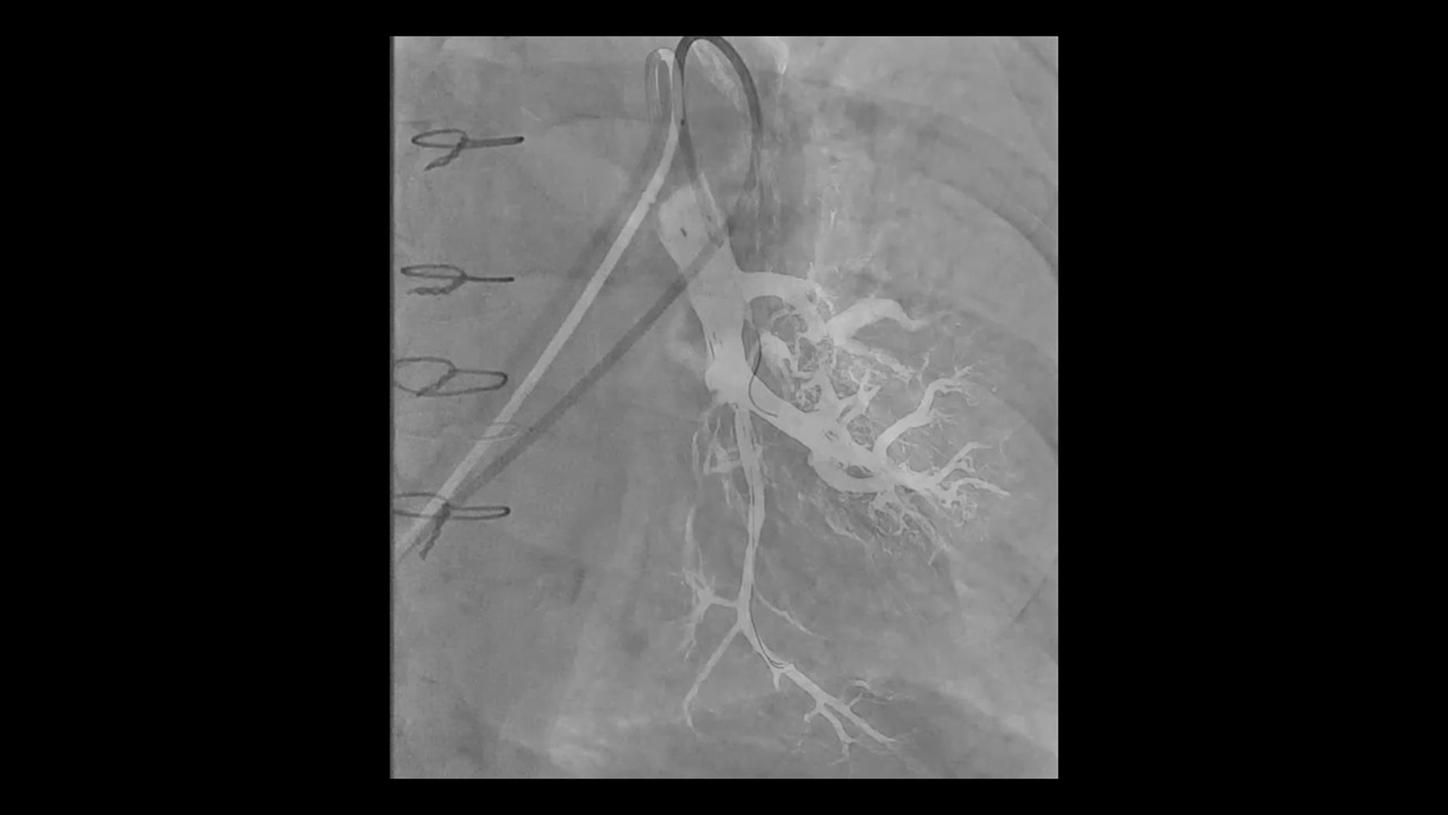

Discover how leading clinicians are transforming interventional radiology with Siemens Healthineers technologies. From ultra-fast 3D imaging to laser-guided needle procedures, the ARTIS icono ceiling powered by OPTIQ and syngo DynaCT are redefining what’s possible in IR. Explore real-world cases, expert insights, and the future of image-guided therapy.